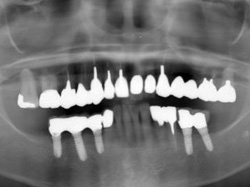

術後レントゲン